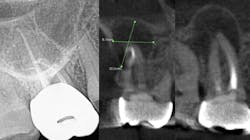

While I am not an expert, I do know that a bacterial infection inside or outside the mouth isn’t stellar for the entire body. In more than 30 years of clinical care, I can’t count the number of times I’ve seen a radiolucent area on a radiograph, when asymptomatic the treatment was nothing. There were other cases where the patient was in pain, given an antibiotic, and sent on their way. They didn’t have a follow-up appointment to treat the infection, perhaps because they couldn’t afford it or didn’t want treatment. I’m assigning no blame here, but simply stressing that we need to continue to educate our patients. Pathogens circulate and sometimes require the body’s immune system to be on overdrive, and many people’s health can’t afford to have an overactive immune system. Technology is expanding and dentistry can now utilize cone beam imaging to find abscesses that don’t present on a 2D radiograph. We can help our patients become healthier. But a silent abscess is an abscess. My friends in a Nashville dental practice recently had a case where the periapical radiograph looked completely fine, yet when a cone beam was done, an abscess showed up louder than Loretta Lynn at the Grand Ole Opry. We should be stewards of new knowledge, new technology, and be open to the expanding world of science.